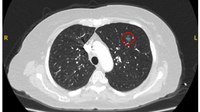

Computed tomography (CT) showing a left upper lobe peripheral nodule with several pleural ‘tags’ and element of retraction of the adjacent pleura. Resection histopathology confirmed a well-differentiated squamous cell lung cancer

From the collection of Dr George Tsaknis, MD, PhD, FRCP(London), MRQA, MAcadMEd, PGCert; used with permission